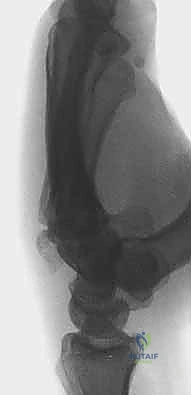

- العظم الهلالي (Lunate): يقع في منتصف الصف القريب، وهو حجر الزاوية في حركة الرسغ. كسوره نادرة ولكنها خطيرة جداً وقد تؤدي إلى انقطاع التروية الدموية (مرض كينبوك).

- النخر اللاوعائي (Avascular Necrosis): موت أنسجة العظم بسبب انقطاع الدم (خاصة في العظم الهلالي).